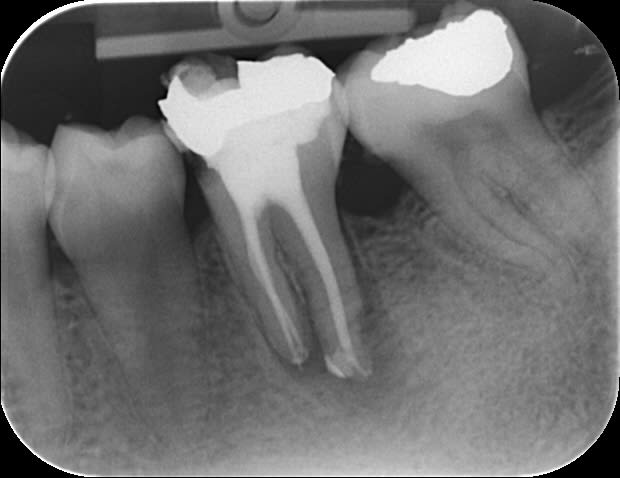

mrquentin

il fallait bien que je me vante auprès de quelqu'un!!! je me suis pris pour le roi du monde pdt 5 minutes ;)

au début je me suis dis: "c'est une fracture ce trait?" sur la radio préop?

cond lat à froid+thermocompactage.

Bien joué !

Sur les constrictions élargies des dents nécrosées on obtient les plus jolis résultats radio.